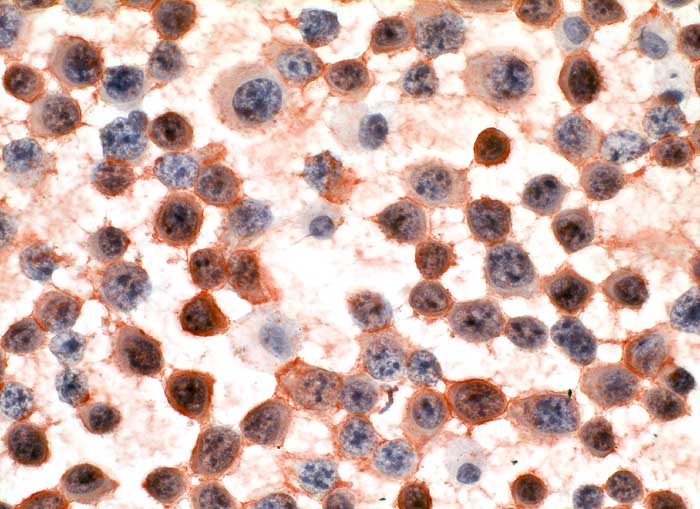

pit/ Multiples Myelom

Multiples Myelom

Die plasmazelluläre Differenzierung eines wenig differenzierten multiplen Myeloms ist oftmals nur andeutungsweise zu sehen. Bei einem wenig differenzierten lymphoiden Tumor sollte deshalb immer auch an das multiple Myelom gedacht werden, insbesondere wenn die Marker für B-Zell Differenzierung negativ sind.